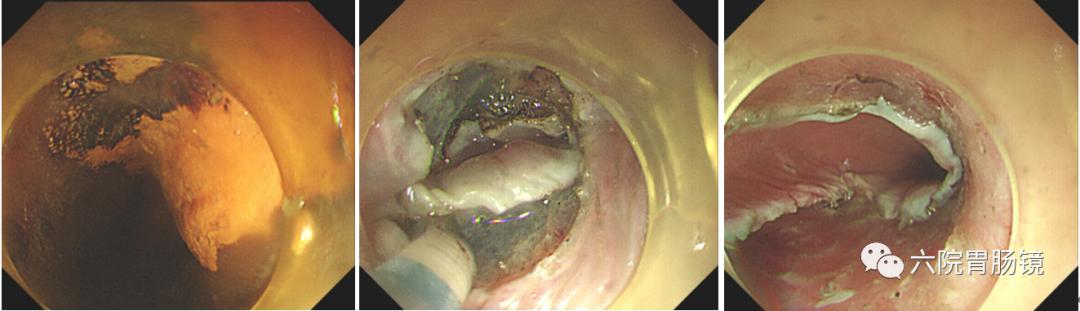

随着内镜技术的不断发展,内镜检查成为目前发现消化道早癌最简便、最有效方法。消化道早癌内镜下通常可表现为粘膜片状发红或发白,粘膜不平整、粗糙,可伴糜烂或结节灶,质地脆或硬、易出血,血管网模糊或消失等。但是有相当一部分消化道早癌的病灶比较小,位置隐蔽,普通白光内镜不容易发现(图1A),除了常规的白光内镜,我们还会使用放大内镜电子染色技术(图1B)、超声内镜(图1C)、化学染色等技术(图1D)帮助发现病灶,评估病灶范围、血管形态、浸润程度与病变性质,使诊断精准度更高,为后续治疗做好准备。

图1早期胃癌内镜下表现A.普通白光内镜检查;B.放大内镜电子染色检查;C超声内镜检查;D内镜下化学染色检查